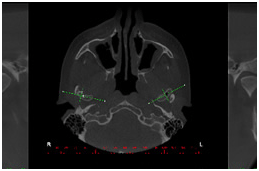

Vista axial Reconstruções 3D